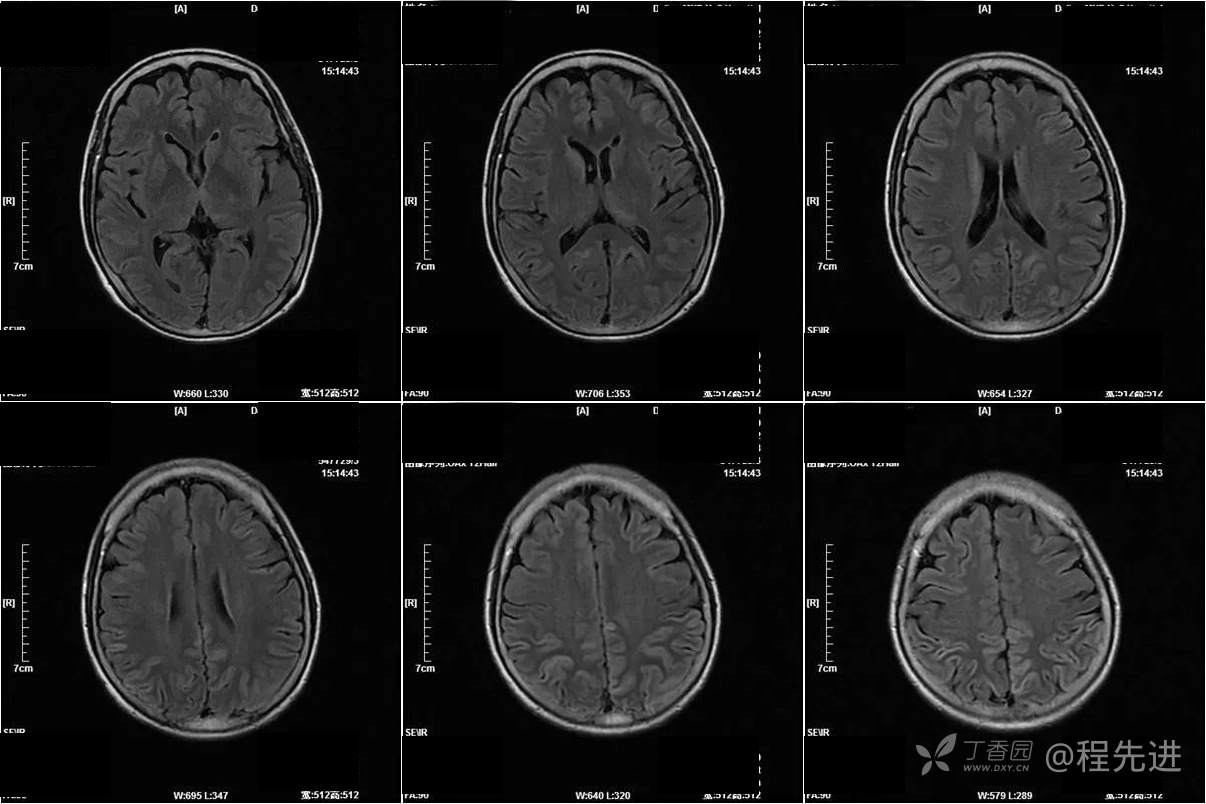

T2FLAIR